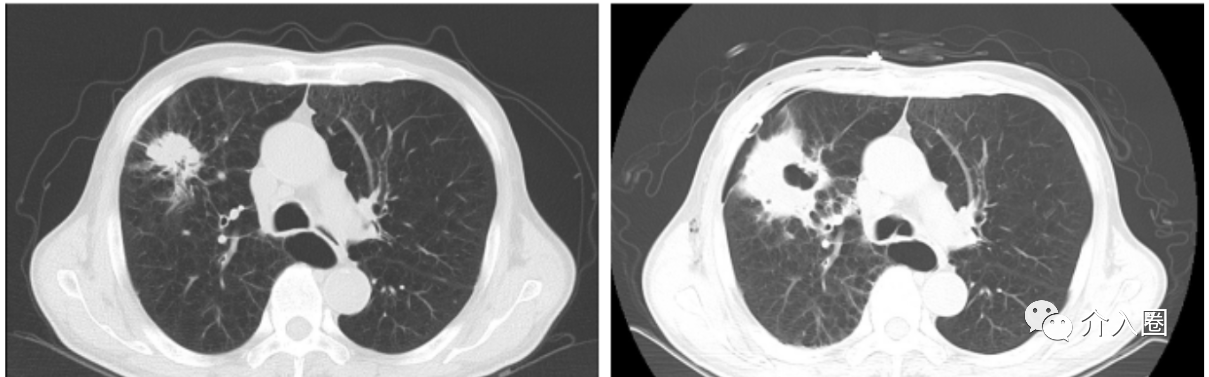

如下圖為消融前后胸部CT對(duì)比。

總的來(lái)說(shuō),冷凍消融作為一種治療高風(fēng)險(xiǎn)肺癌的新興方法,顯示出了潛力和前景。